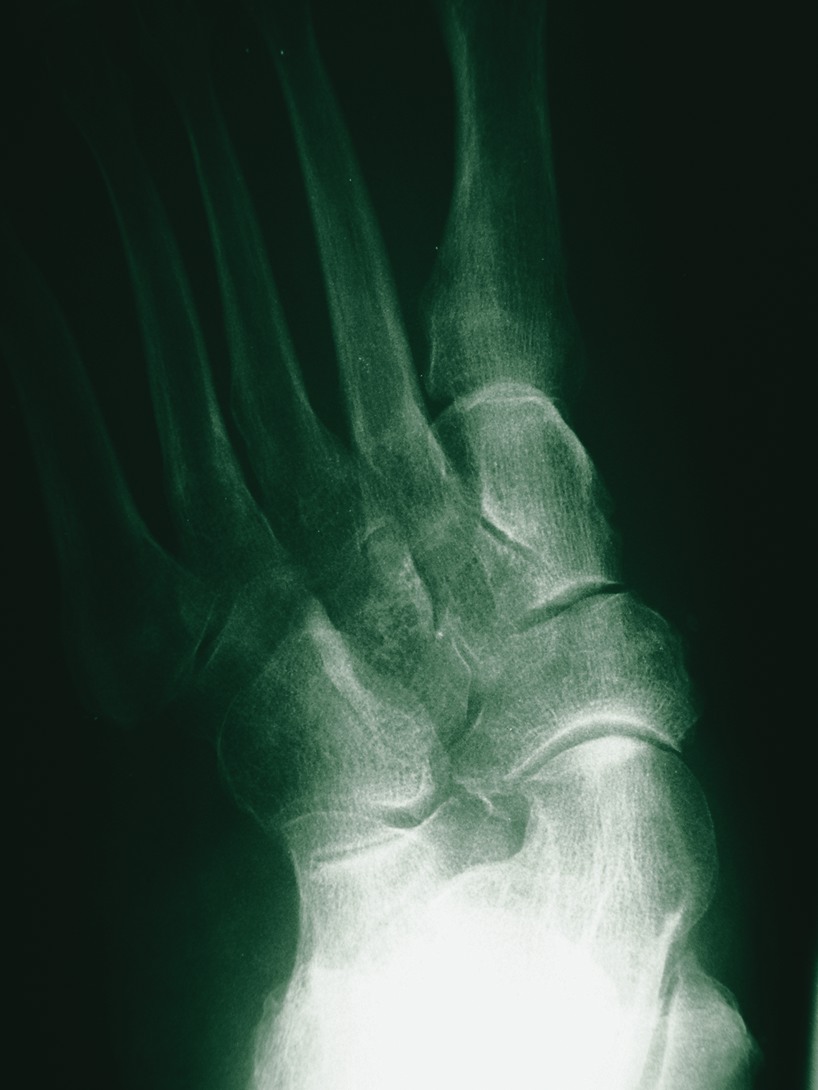

A diabetic patient presented with severe posterior tibial tendon dysfunction and pes plano valgus deformity. Surgeons performed a triple arthrodesis and applied the EZ Frame with four pins. The pins were located in the calcaneus, talus, navicular and across the metatarsals (see right photo). The patient should remain non-weightbearing for up to six weeks. At this time, practitioners can remove the frame and place the patient in a below knee walking cast for approximately two weeks following serial radiographs. One can subsequently transition the patient into a CAM-Walker and eventually into regular shoe gear. The obvious advantages to employing this modality for diabetic foot reconstruction are guarded weightbearing, enhanced stability and the preclusion of proximal pin sites. Dr. Duckworth is a first-year resident at the Southeast Michigan Surgical Hospital in Warren, Mich. Dr. Steinberg (pictured) is an Assistant Professor in the Department of Surgery at the Georgetown University School of Medicine in Washington, D.C. He is a Fellow of the American College of Foot and Ankle Surgeons.